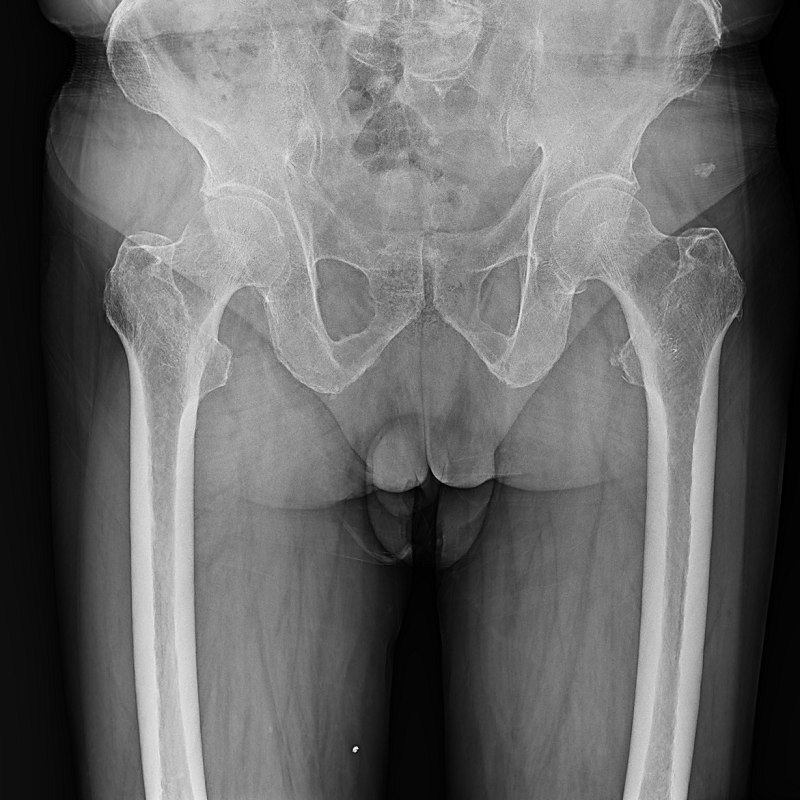

●呈現(xiàn)全下肢或全脊柱圖像

●在脊柱及下肢畸形矯正手術(shù)治療中,為術(shù)前方案制定和術(shù)后復(fù)查提供精準(zhǔn)測(cè)量

●有效解決傳統(tǒng)X光片不能一次成像問(wèn)題,為患者提供更加優(yōu)質(zhì)的醫(yī)療服務(wù)

點(diǎn)片裝置可實(shí)現(xiàn)大范圍縱向移動(dòng),高效完成各部位、全身拼接等檢查需求